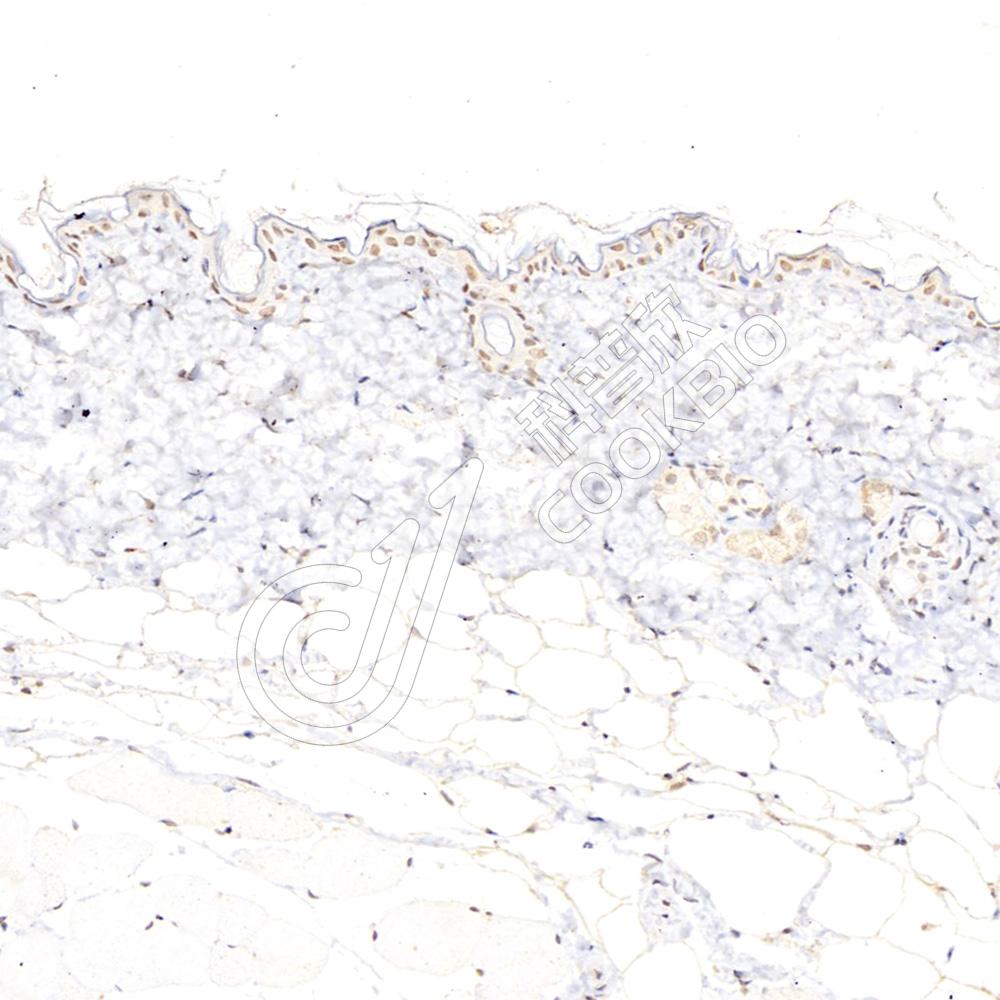

IHC检测p21蛋白(货号 K236459).

样品: 小鼠皮肤, 4%多聚甲醛 (货号KSG1101) 固定12-24小时.

抗原修复: 柠檬酸抗原修复液(干粉, pH 6.0) (KSG1201), 高压锅均匀喷气计时2分钟.

—抗: 1: 1000稀释, 4℃ 孵育过夜.

二抗: S-vision免疫组化多聚二抗(山羊抗小鼠), 即用型(货号KB3903), 室温孵育20分钟.